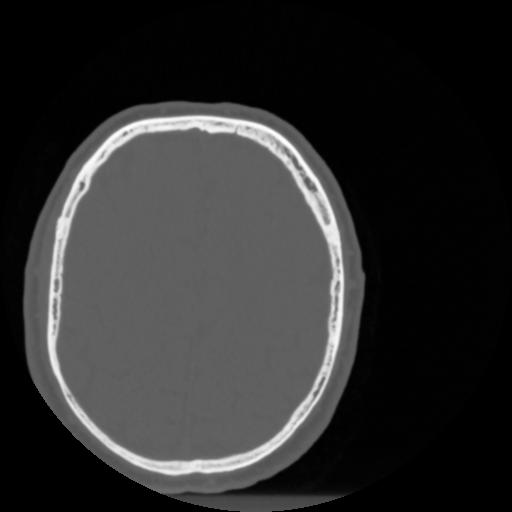

4 CEREBRO,,Vol,0.5,CEREBRO,,